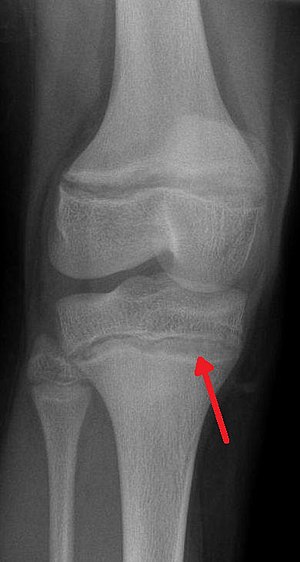

| An X ray demonstrating the characteristic finding of lead poisoning in humans—dense metaphyseal lines. | |

Exposure to lead can occur by contaminated air, water, dust, food, or consumer products.[2] Children are at greater risk as they are more likely to put objects in their mouth such as those that contain lead paint and absorb a greater proportion of the lead that they eat.[2] Exposure at work is a common cause of lead poisoning in adults with certain occupations at particular risk.[7] Diagnosis is typically by measurement of the blood lead level.[2] The Centers for Disease Control (US) has set the upper limit for blood lead for adults at 10 µg/dl (10 µg/100 g) and for children at 5 µg/dl.[8][9] Elevated lead may also be detected by changes in red blood cells or dense lines in the bones of children as seen on X-ray.[4]

Blood lead levels are an indicator mainly of recent or current lead exposure, not of total body burden.[171] Lead in bones can be measured noninvasively by X-ray fluorescence; this may be the best measure of cumulative exposure and total body burden.[21] However this method is not widely available and is mainly used for research rather than routine diagnosis.[85] Another radiographic sign of elevated lead levels is the presence of radiodense lines called lead lines at the metaphysis in the long bones of growing children, especially around the knees.[172] These lead lines, caused by increased calcification due to disrupted metabolism in the growing bones, become wider as the duration of lead exposure increases.[172] X-rays may also reveal lead-containing foreign materials such as paint chips in the gastrointestinal tract.[16][172]